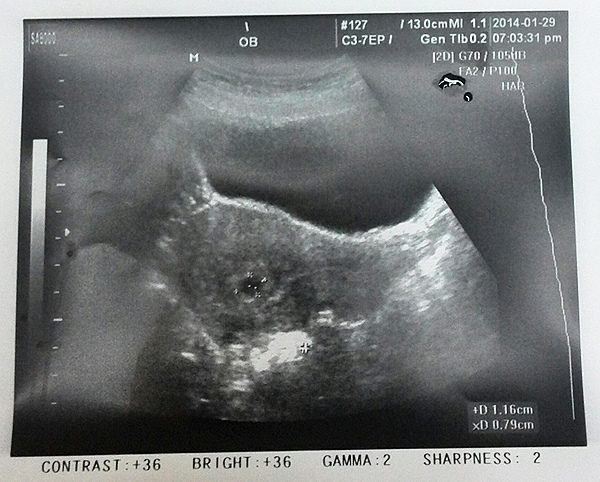

2014 / 01 / 29

第一次到婦幼檢查,確認懷孕四週,無子宮外孕